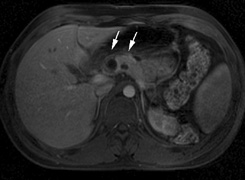

- Hypertension.22 There is increased incidence of aortic coarctation and pheochromocytomas. Retroperitoneal

neurofibromas may compress the renal artery. These

complications may manifest as hypertension in affected children